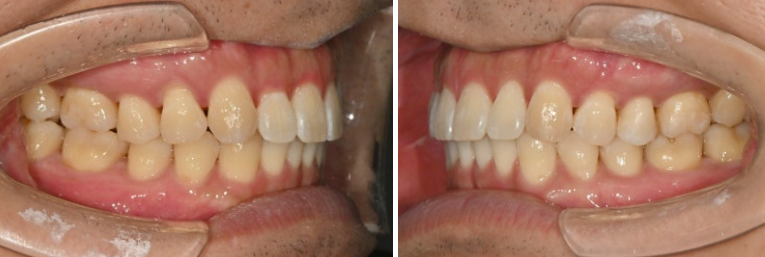

이제 전후 볼까요

24.11~25.10

앞니 사이 벌어진 공간은 없어졌고 다시 벌어지지 않도록 고정식 철사 유지장치로 단단히 고정되었습니다

쓰러진 큰어금니가 잘 섰습니다.

가위교합의 개선으로 서로 엇갈려 물리지 못하던 큰어금니가 이제 잘 교합이 됩니다.

코와 인중과 어긋나 있던 중심선이 얼굴과 맞아지면서 대칭성이 돋보입니다.

벌어져 있던 앞니공간을 이용하여 돌출감도 어느정도 개선이 되었고